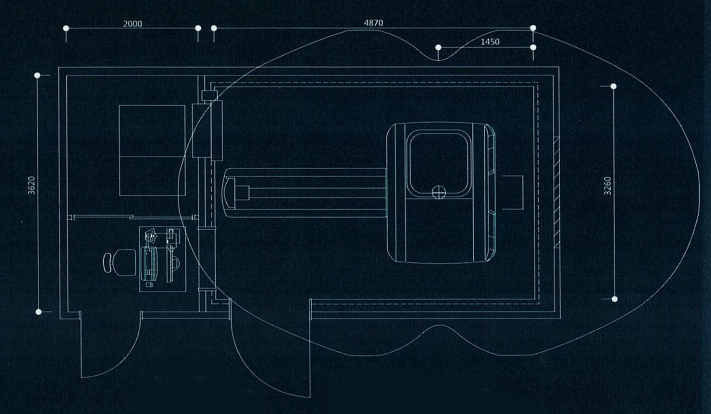

贴墙式设计,全设备最小占地23平米,设置面积比原来小了43%、更可以减少MRI检查室的防护板材料的使用

最小安装布局图纸举例最小面积

MR检查室:15.9平米操作

机房:7.2平米

系统共计:23.1平米

·布局图会根据房间形状和周围环境改变

·机房屏蔽请联系专业厂家

MR检查室:15.9平米操作

机房:7.2平米

系统共计:23.1平米

·布局图会根据房间形状和周围环境改变

·机房屏蔽请联系专业厂家